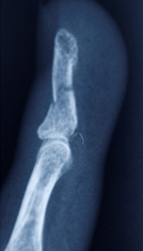

AÇIK EL KIRIKLARI

EL KIRIKLARI

Kırıklar, el ve bilekteki kemiklerin makine veya aletlerden kaynaklanan darbeyle veya düşüp elin üzerine inilmesiyle kırılmasıyla meydana gelir. Bunlar kapalı (açık yara yok) veya açık (kırık kemik uçlarının yakınında açık yara) olabilir.

DİSTAL FALANKS KIRIKLARI

Distal falanks, parmak ucundaki kemiktir. Uygun parmak fonksiyonu ve tırnak büyümesi için sabit bir distal falanks gerekir. Çoğu distal falanks kırığının düzeltilmesi gerekmezken, bazılarının düzeltilmesi gerekir. Bunlar, düzgün bir şekilde birleştirilmesi gereken birçok parça ile oldukça karmaşık olabilir. Kötü bir şekilde düzeltilmiş kırıklar iyi iyileşmez, çok fazla ağrıya neden olur ve işe dönüşü geciktirir.

AÇIK EL KIRIKLARI

Açık el kırıkları, kemiğin tüm kirlerinden temizlenmesi ve sabitlenmesi için mümkün olan en kısa sürede ameliyat edilmelidir. Bu, enfeksiyon riskini azaltır ve sertliği önlemek için erken rehabilitasyona olanak tanır.

ELİN KAPALI KIRIKLARI

Eldeki kapalı kırıklar, yerinden oynamışsa veya deformiteye neden oluyorsa, uygun hizaya geri konulmalı ve ele iyi bir fonksiyon kazandırmak için metal teller, vidalar veya plakalarla sabitlenmelidir. Bu, el yaralanmasından birkaç gün sonra, mümkün olan en kısa sürede erken rehabilitasyona izin vermek için en iyi şekilde yapılır.

Beşinci metakarpalın boynundaki kırık, kliniğimizde çok yaygındır. Volar plaka fiksasyonu, erken mobilizasyona izin verdiği ve ekstansör tendon yapışmasını önlediği ve cerrahi yara izi yerleşiminin avuç içinde olması nedeniyle tercih ettiğimiz tedavi yöntemidir.